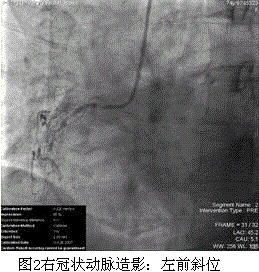

问题 患者女,74岁,主因“间断胸痛20余年,加重2个月”入院。5年前行冠状动脉造影检查示右冠状动脉完全闭塞,前降支弥漫病变,于前降支近中段植入支架3枚。此后患者仍偶有胸痛发作。2个月前,开始出现活动中胸痛,以饱餐后为著,且症状逐渐加重,活动耐量逐渐降低。既往:原发性高血压史10余年,糖尿病史4年。入院查体:Bp 140/70 mmHg。双肺呼吸音清,未闻及干、湿啰音。心界不大,心律不齐,可闻及期前收缩约5次/min。肝、脾肋下未及。双踝部轻度可凹性水肿。ECG检查:房性期前收缩二联律。 对于此患者适当的治疗策略是(提示 入院后UCG检查:左心室肥厚,舒张功能减低;左心房扩大;LVEF:61%。主要实验室检查结果:CK-MB 0.6 ng/ml,cTnI 0.01ng/ml,Scr 133 μmol/L。冠状动脉造影结果(图1、2):左冠状动脉:LAD中段原支架内狭窄50%60%,LCX近段狭窄70%80%;右冠状动脉:近段弥漫病变,自中段完全闭塞。